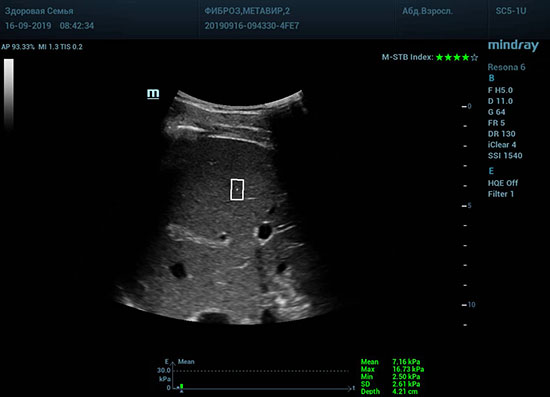

Определение плотности печени. Не ошибся ли оператор при измерении эластических свойств печени? Для оценки критериев качества предусмотрен индекс MBT, который покажет насколько «твердой» была рука оператора и двигалась ли печень. При MBT 5* рука тверда и показатели достоверны. Для оценки качества результатов используется IQR индекс, отображающий колебания показателей в точке измерения при расчете медианы. Показатели при IQR <30% считаются приемлемыми. Техника сканирования через межреберные промежутки требует размещение окна интереса на несколько сантиметром ниже капсулы, для исключения эффекта реверберации. Установка ROI на паренхиму без захвата сосудов, для исключения погрешностей измерения.

Стадия фиброза определяется по системе METAVIR Staging, построенной на данных биопсии и сопоставлении с данными эластографии. Своевременная диагностика фиброза, и начало его лечения, залог благоприятного исхода заболевания.

• METAVIRF2 – Портальный фиброз с вовлечением нескольких перегородок